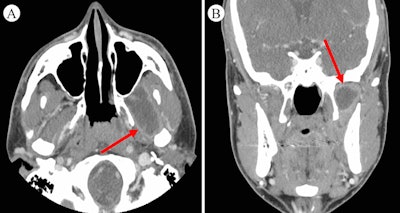

A maxillofacial CT scan reveals an infratemporal fossa abscess of the man's lateral pterygoid. A: Axial CT of the abscess. B: Coronal CT of the abscess.

A maxillofacial CT scan reveals an infratemporal fossa abscess of the man's lateral pterygoid. A: Axial CT of the abscess. B: Coronal CT of the abscess.Draining the abscess reduced the swelling, but the man was still admitted to a hospital for observation and given intravenous antibiotics. Despite the aspiration, the patient again experienced chills, continued fever, swelling, trismus, and pain. The lab results showed an elevated white blood cell count, and clinicians performed an operative incision and drainage, according to the report.